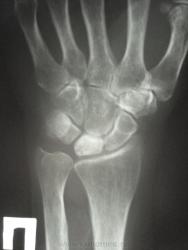

женщина, 1956 года рождения, жалобы на боли в правой лучезапястном суставе в течение полу года, травму отрицает. Кроме остеохондропатии полулунной кости в голову ничего не приходит. Ваше мнение коллеги))))))))

Скоро наступит патологический перелом...

Остеохондропатия - удел детского возраста. Здесь, думаю, правильнее говорить об асептическом некрозе.

Остеохондропатия (греч. οστεοχονδροπαθια) – асептический некроз губчатой кости, протекающий хронически и дающий осложнения в виде микропереломов. Остеохондропатии являются следствием местных расстройств кровообращения, возникающих в результате воздействия различных факторов: врождённых, обменных, травматических и др.